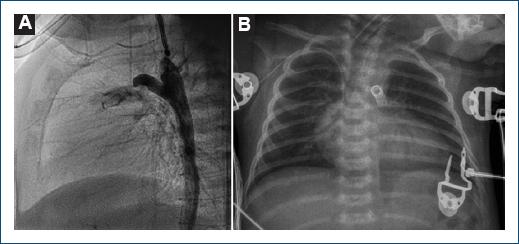

Los procedimientos fueron llevados a cabo en el servicio de hemodinamia del Hospital Garrahan, formado por cuatro hemodinamistas con años de experiencia en el tratamiento de cardiopatías congénitas de pacientes recién nacidos. La distribución de los casos fue similar entre estos. Todos los pacientes fueron planteados para el procedimiento luego de realizar el diagnóstico inicial con ecocardiograma. En algunos casos fue necesario realizar angio-TC con contraste para definir adecuadamente la morfología del conducto, y en unos pocos casos el cateterismo diagnóstico inicial se utilizó para plantear la posibilidad de implantar un stent ductal. En la actualidad se encuentra protocolizada la realización de angio-TC en aquellos pacientes en quienes se plantee la colocación de un stent en el conducto arterioso para definir con mayor certeza la morfología ductal. En los casos que correspondía se suspendió el goteo de prostaglandinas 12 horas antes para favorecer la constricción pulmonar. Para el procedimiento, todos los pacientes requirieron anestesia general con asistencia respiratoria mecánica. En la mayoría de los casos el acceso vascular utilizado fue tanto arterial como venoso, y los introductores oscilaron entre 3 y 5 Fr. En cuatro pacientes el acceso arterial fue carotídeo por el origen del conducto arterioso desde el tronco braquiocefálico. Se utilizaron stents coronarios no farmacológicos con diámetros entre 3.5 y 4.5 mm y de longitud variable. En siete casos fue necesario el implante de dos stents para mantener la permeabilidad del conducto arterioso (Figs. 1 y 2). Al finalizar el procedimiento se efectuó angiografía de control para certificar el buen funcionamiento del stent y su permeabilidad, y luego, con una saturación acorde al modelo hemodinámico, se finalizó el procedimiento y los pacientes pasaron a la unidad de cuidados intensivos (Fig. 3). Posterior al procedimiento se encuentra protocolizado mantener anticoagulación con heparina por 48 horas y luego iniciar antiagregación con ácido acetilsalicílico.

Figura 4 A: angiografía en un paciente con anomalía de Ebstein con atresia pulmonar que evidencia un conducto arterioso con origen en la aorta descendente. B: radiografía de tórax de control que evidencia cardiomegalia a expensas de la aurícula derecha, arco pulmonar excavado y punta elevada con normal posicionamiento del stents ductal.